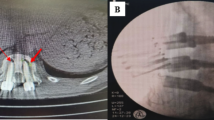

A 69-year-old female (T = −3.6) who was treated with unilateral 2 CICPSs fixation by PMMA augmentation. (A,B) Preoperative extension and flexion radiographs indicated the L4 vertebral body was unstable and displaced forward. PMMA seemed to leak to the anterior vertebral body. (C,D) The postoperative radiographs showed lumbar sequence reconstruction. (E,F) Three years after surgery, CT showed bony fusion achieved (the red arrow).

A 64-year-old female (T = −3.8) who was treated with bilateral 4 CICPSs fixation by PMMA augmentation. (A,B) Preoperative radiographs indicated the L4 spondylolisthesis. (C,D) The postoperative radiographs showed lumbar sequence reconstruction. (E,F) CICPSs was observed in place after 6 months of surgery and bony fusion was achieved.